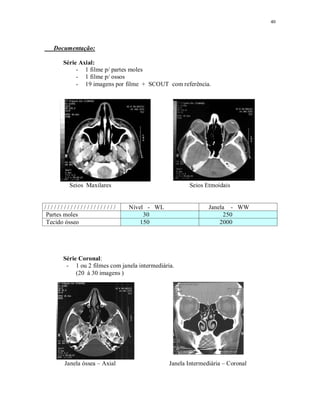

Documentação:

Série Axial:

- 1 filme p/ partes moles

- 1 filme p/ ossos

- 19 imagens por filme + SCOUT com referência.

Seios Maxilares Seios Etmoidais

/ / / / / / / / / / / / / / / / / / / / / / Nível - WL Janela - WW

Partes moles 30 250

Tecido ósseo 150 2000

Série Coronal:

- 1 ou 2 filmes com janela intermediária.

(20 à 30 imagens )

Janela óssea – Axial Janela Intermediária – Coronal

Janela Intermediária 100 1500